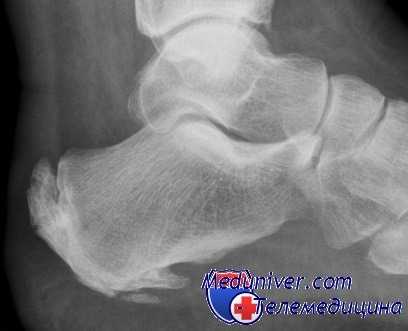

Пяточный эпифизит (болезнь Севера), наблюдаемое у детей, обычно мальчиков в возрасте 9—14 лет. Оно представляет собой вялотекущую воспалительную реакцию в заднем эпифизе пяточной кости, который, в отличие от остальной пяточной кости, имеет отдельный центр окостенения. Последний появляется у ребенка в возрасте 10 лет и сливается с пяточной костью в возрасте 15 лет.

Пациент жалуется на боль в заднем отделе пятки ниже места прикрепления ахиллова сухожилия, которая усиливается при стоянии на пальцах или беге. Начало постепенное, больной отмечает облегчение при расслаблении мышц голени при согнутом коленном суставе и стопе в положении эквинуса. Болезненность наиболее выражена по внутренней и наружной сторонам, где эпифизарная пластинка расположена подкожно.

Рентгенограммы в ранней стадии обычно неинформативны. Позже, однако, при сравнении со здоровой стороной можно определить фрагментацию эпифиза.

Заболевание — самокупирующееся, при рецидивах лечение симптоматическое до закрытия эпифизарной линии. Рекомендуется уменьшить натяжение ахиллова сухожилия, подложив под пятку прокладку толщиной 0,6 см для выведения стопы в положение эквинуса, а также назначить покой и обезболивающие средства. В тяжелых случаях может потребоваться иммобилизация стопы гипсовой повязкой в положении эквинуса.